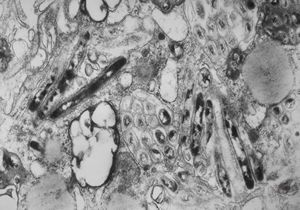

M,54y. | Whipple disease

Whipple disease